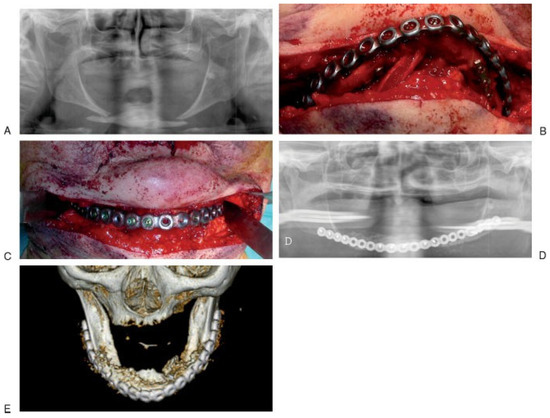

The first group included eight patients treated using 2.0-mm locking large-profile bone plates. All patients were female, ranging in age from 77 to 91 years (mean, 80 years; Table 2; Figure 2). Causes of fracture included six accidental falls, one motor vehicle accident, and one trauma secondary to assault. Of the eight fractures studied, two were unilateral and six were bilateral. Three of them were located bilaterally at the body region of mandible; in the other three cases, two contralateral angular fractures and one contralateral condylar fracture were associated with the fracture of the body, respectively. The two unilateral fractures were located at the mandibular body. All fractures were displaced. In two cases, displacement of bone segments was mild; in the other six, fractures displacement was moderate. All surgical approaches were extraoral: seven submandibular (of these five were bilateral) and one submental. Temporary fixation was applied to seven fractures before the final fixation plate was adapted and secured. In all cases, temporary fixation devices were removed after the application of the final fixation (Figure 3A–F).

Figure 3. A case of unilateral fracture of the atrophic mandibular body (right). (A) Pretreatment panoramic radiograph showing mandibular body fracture. (B) Computed tomography (CT) axial scan with 3-D reconstruction representing the fracture. (C) Intraoperative photograph showing the 2.0-mm lock large bone plate placed and adapted on the fracture site; meanwhile fracture segments were reduced using temporary fixation devices. (D) Intraoperative photograph showing the 2.0-mm lock large-bone plate fixed and stabilized on the fracture. (E) Postoperative panoramic radiograph demonstrating the reduction and fixation of the fracture provided by the plate. (F) CT scan with 3-D reconstruction.